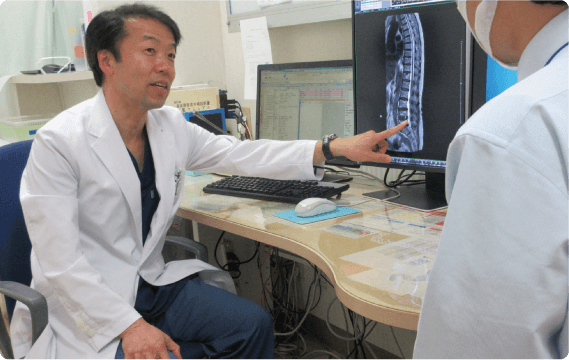

シムラ病院では増え続ける手術件数に対応できるよう、手術室を3部屋に増設しました。整形外科領域においては、広島大学四肢外傷講座と連携し、一般外傷から難易度の高い外傷手術まで幅広い整形外傷手術医療を提供しています。また、低侵襲で最先端の高度診療技術を活用した脊椎手術には自信があり、人工関節・スポーツ外傷に至るまで様々な分野における質の高い手術をお約束いたします。

脊椎

患者さまの高齢化に伴い、脊椎疾患に対しても集学的な治療が必要となっております。整形外科医のみで治療するのではなく、内科医や外科医、麻酔科医が患者さまの治療に協力して参加することにより、全身状態の正確な把握と管理、合併症の早期発見と早期治療、術後疼痛の少ない手術、早期リハビリテーション介入、早期退院が可能となっております。